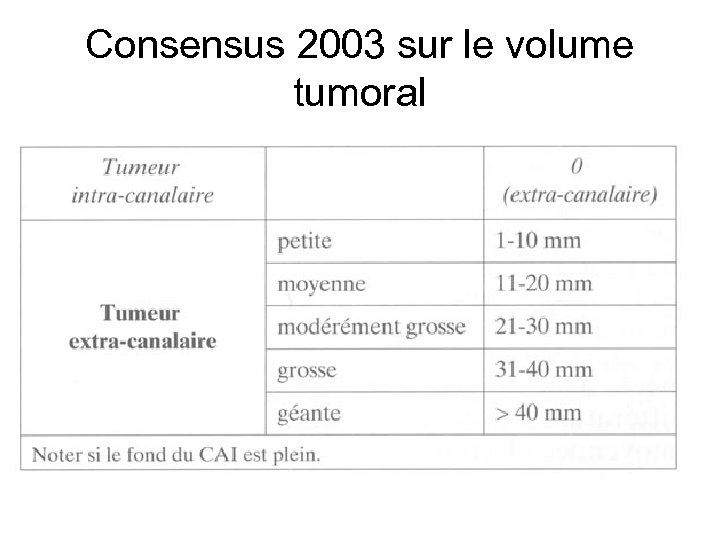

Consensus 2003 sur le volume tumoral

Consensus 2003 sur le volume tumoral